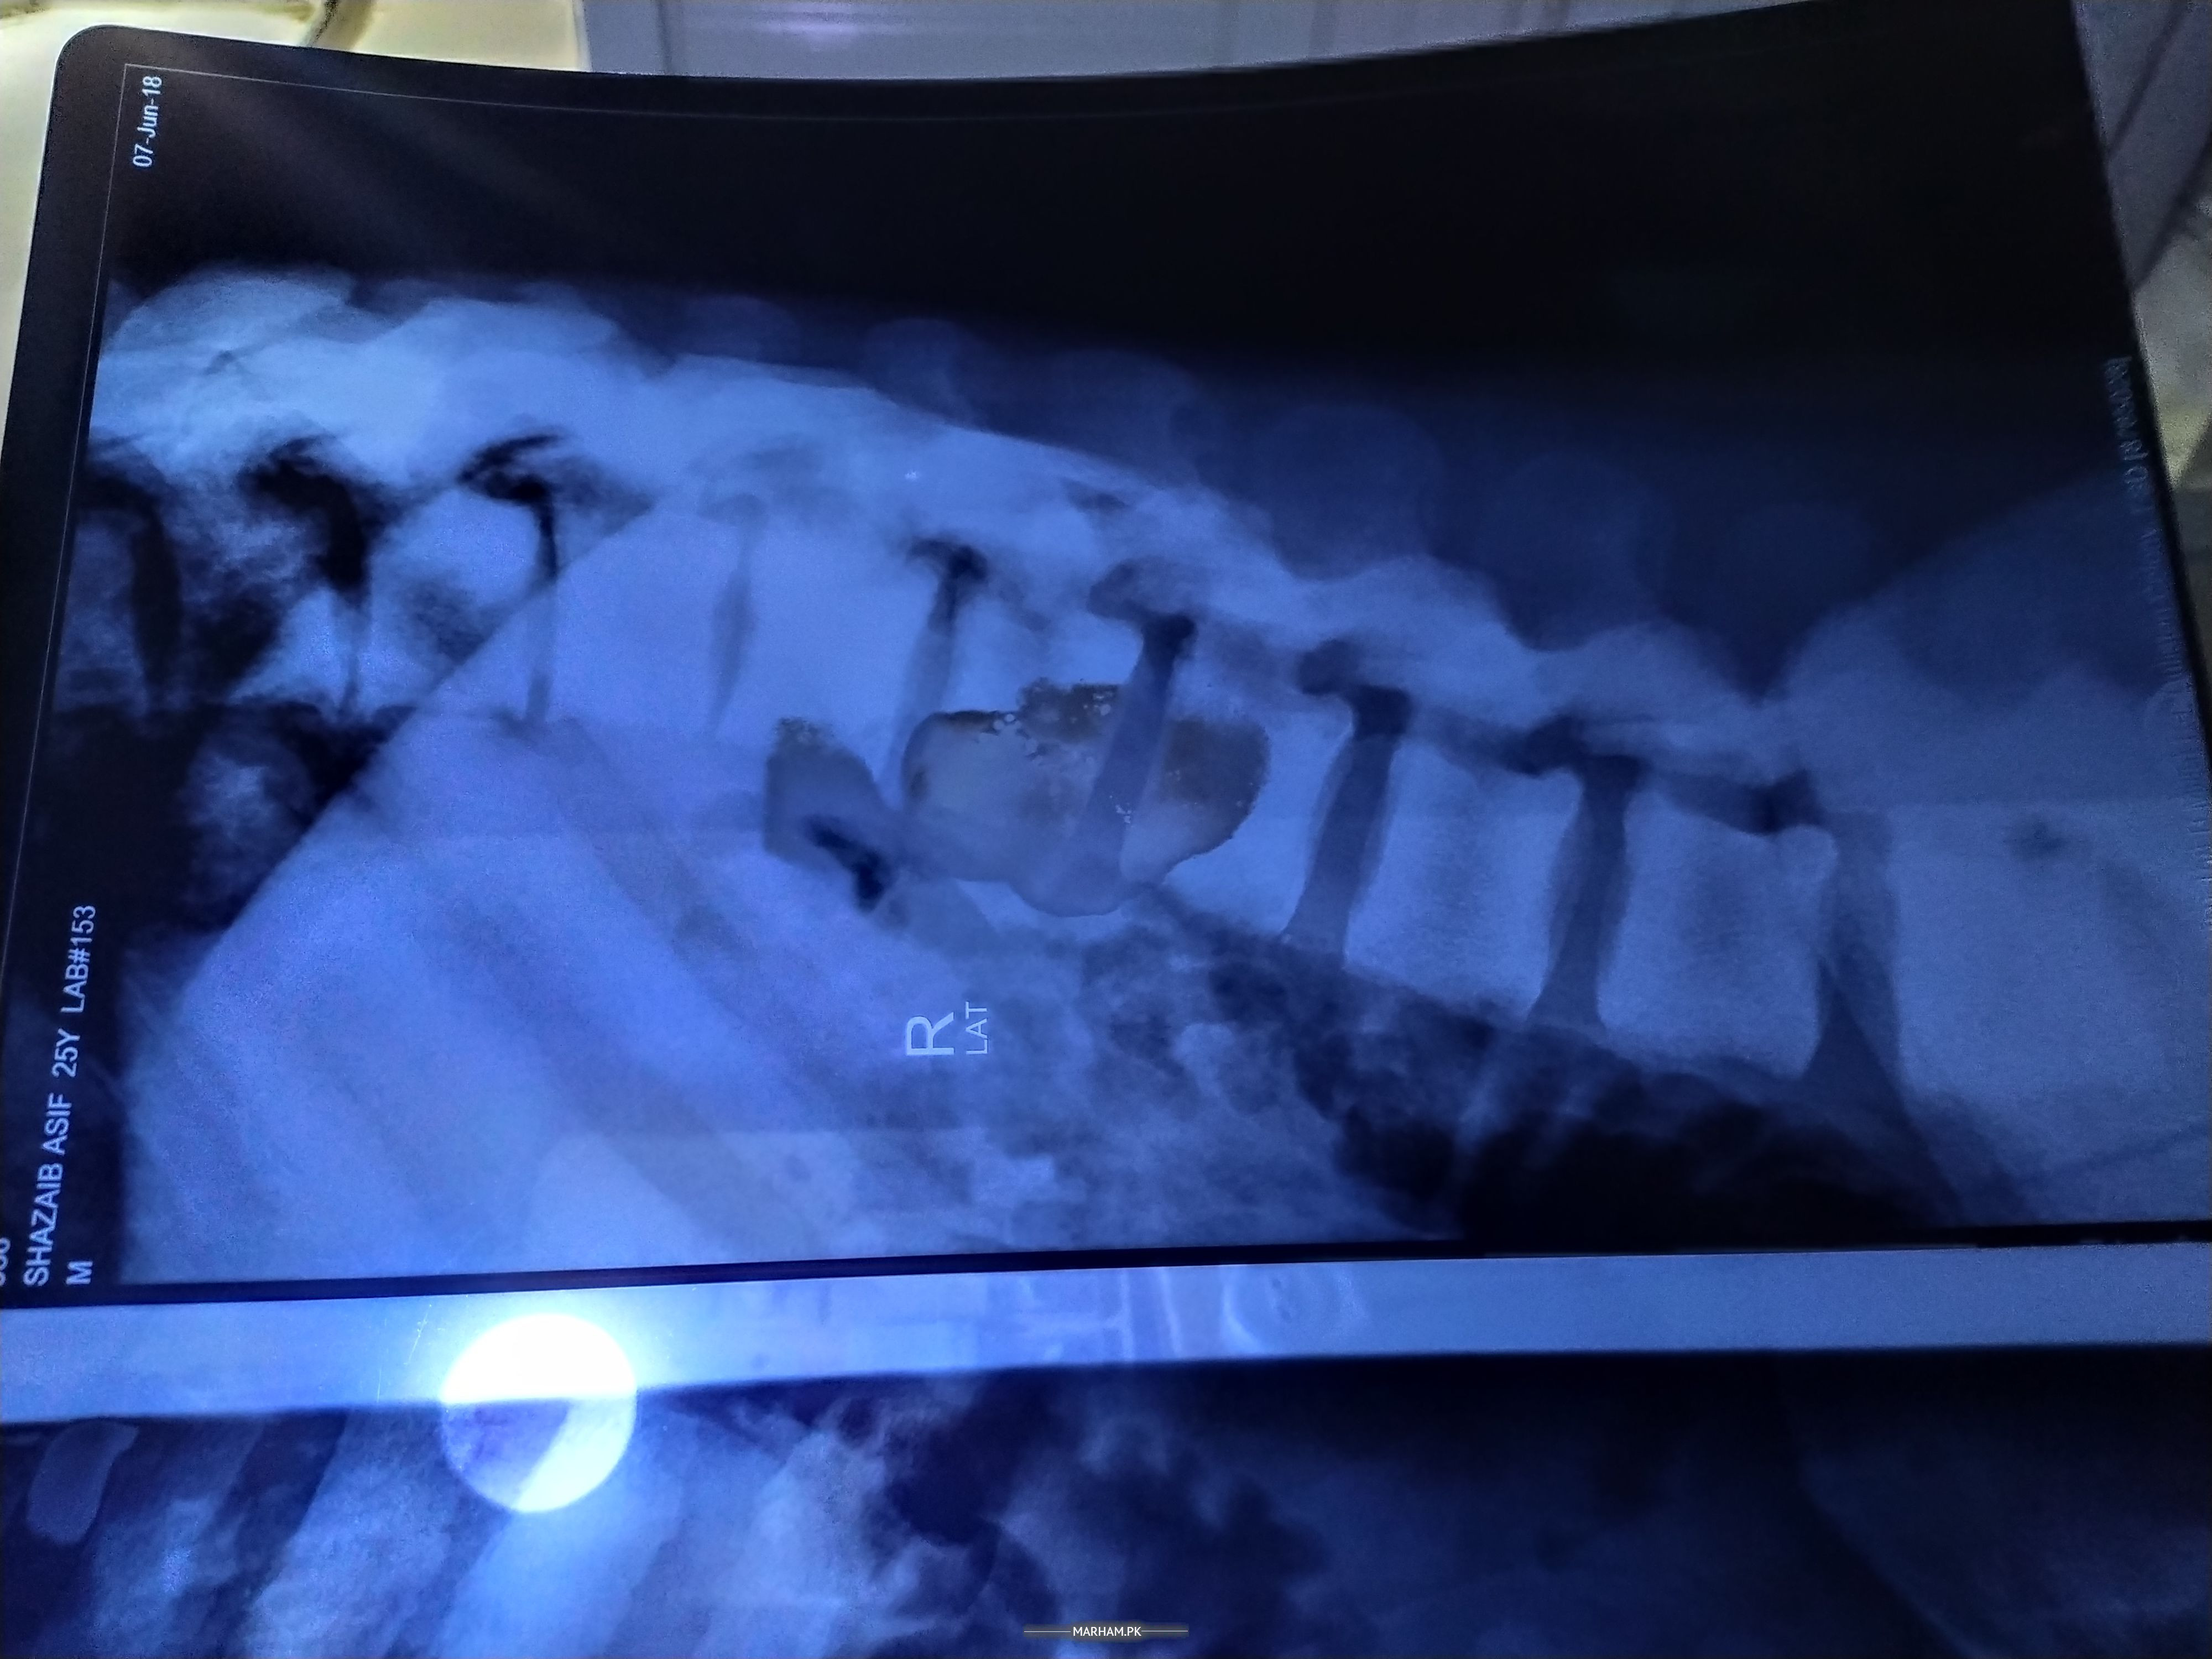

hi doctor, I'm shahzaib from Faisalabad. I'm kidney patient and on dialysis for 2 years. under treatment from SIUT hospital karachi. I'm also having back problem. I have back pain. There is also a tilt in the waist. I am not being treated. I am not being transplanted due to a waistk problem. I'm done 3 times MRI and a rectal biopsy. my HLA B27 is negative. I'm so worried

sir maine report attach ki hai. plzzz check

sir maine MRI report attach ki hai. plzzz check

g sir, x rays bhi hoye hen. 3 MRI hoye hen. kafi saray blood test bhi hoye hen. aur finally rectal biopsy hoi thi. sacroiliac MRI k baad rectal biopsy hoi thi

you have multilevel disc bulges which is due to excessive compression on these spinal joints, and then you have a compensatory pelvic tilt putting pressure on your sacroiliac joint and one of you hip joint as well this is a chain reaction because as I mentioned before your joints are compensating due to an underlying cause which assuming you didn't lift anything heavy in the wrong position, is either because you have pronation in feet or due to hypolododic curve, resulting in poor weight distribution and changing your center of gravity when you walk or stand for too long. did you get spinal xrays as well?

sir mere pas aik purani sine xray report prhi thi 2018 ki, us waqat bhi masla tu tha, wo report main share karta hn. new 1,2 din tak karwaon ga

Aslam o alaikum. sir dr asadullah, mere pas aik purani spine xray report prhi thi, tab bhi masla tu tha, wo main share kar rhaa hn, new report 1,2 din tak krwaon ga. plzzz check